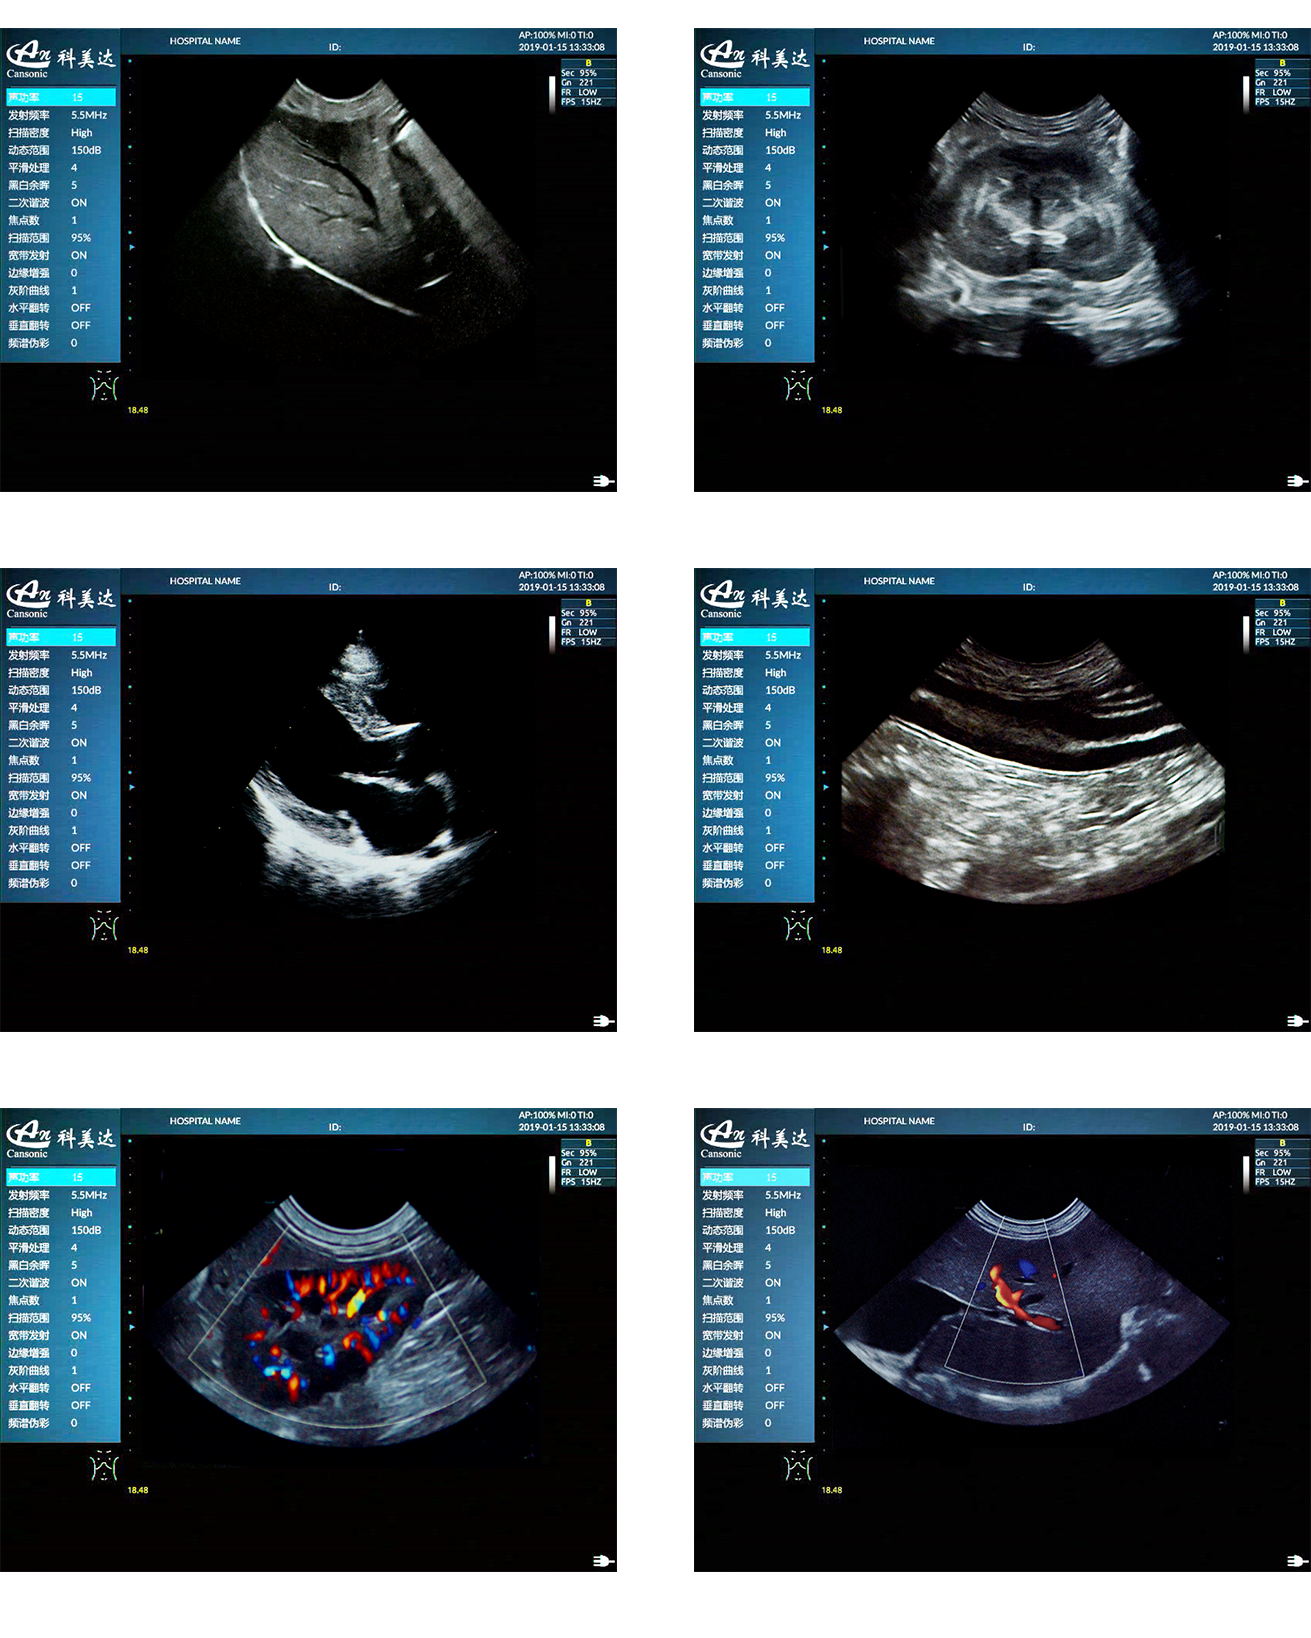

臨床圖示

1、超高性價比便攜獸用彩超,以優(yōu)異的產(chǎn)品性能,提供豐富的動物彩超診療方案

2、適用于狗、貓、馬、牛、羊等多種動物的腹部、生殖、血管小器官,肌骨等檢查模式

5、能量多普勒POWER成像模式、彩色多普勒Color成像模式等模式適用于應(yīng)用掃查